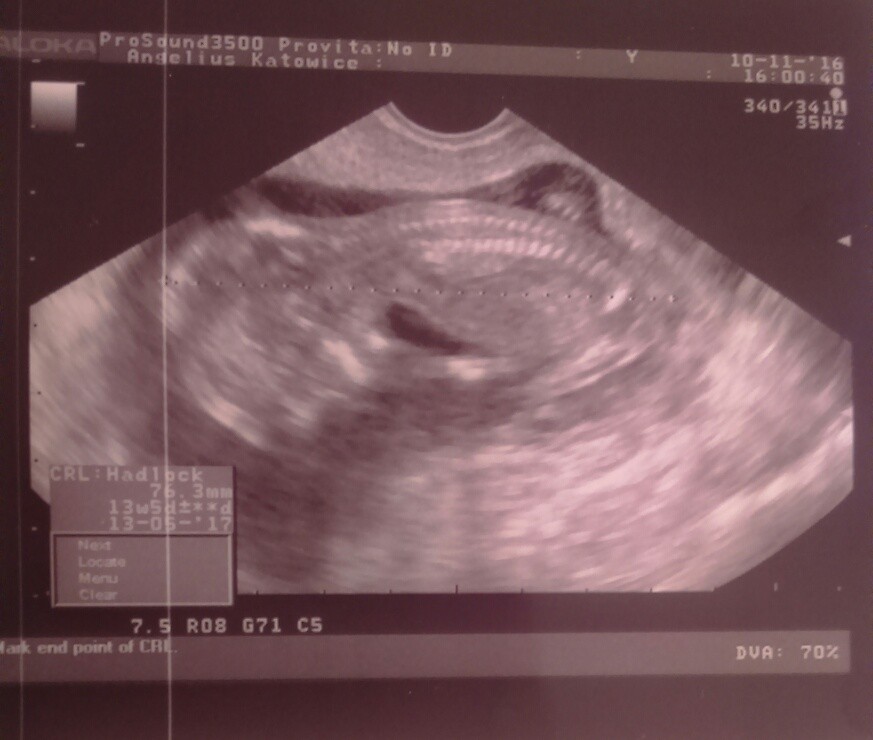

5: rybka14 - 2 badania prenatalne

7:ema51 - badania prenatalne

21: butterfly1331 - 2 badania prenatalne